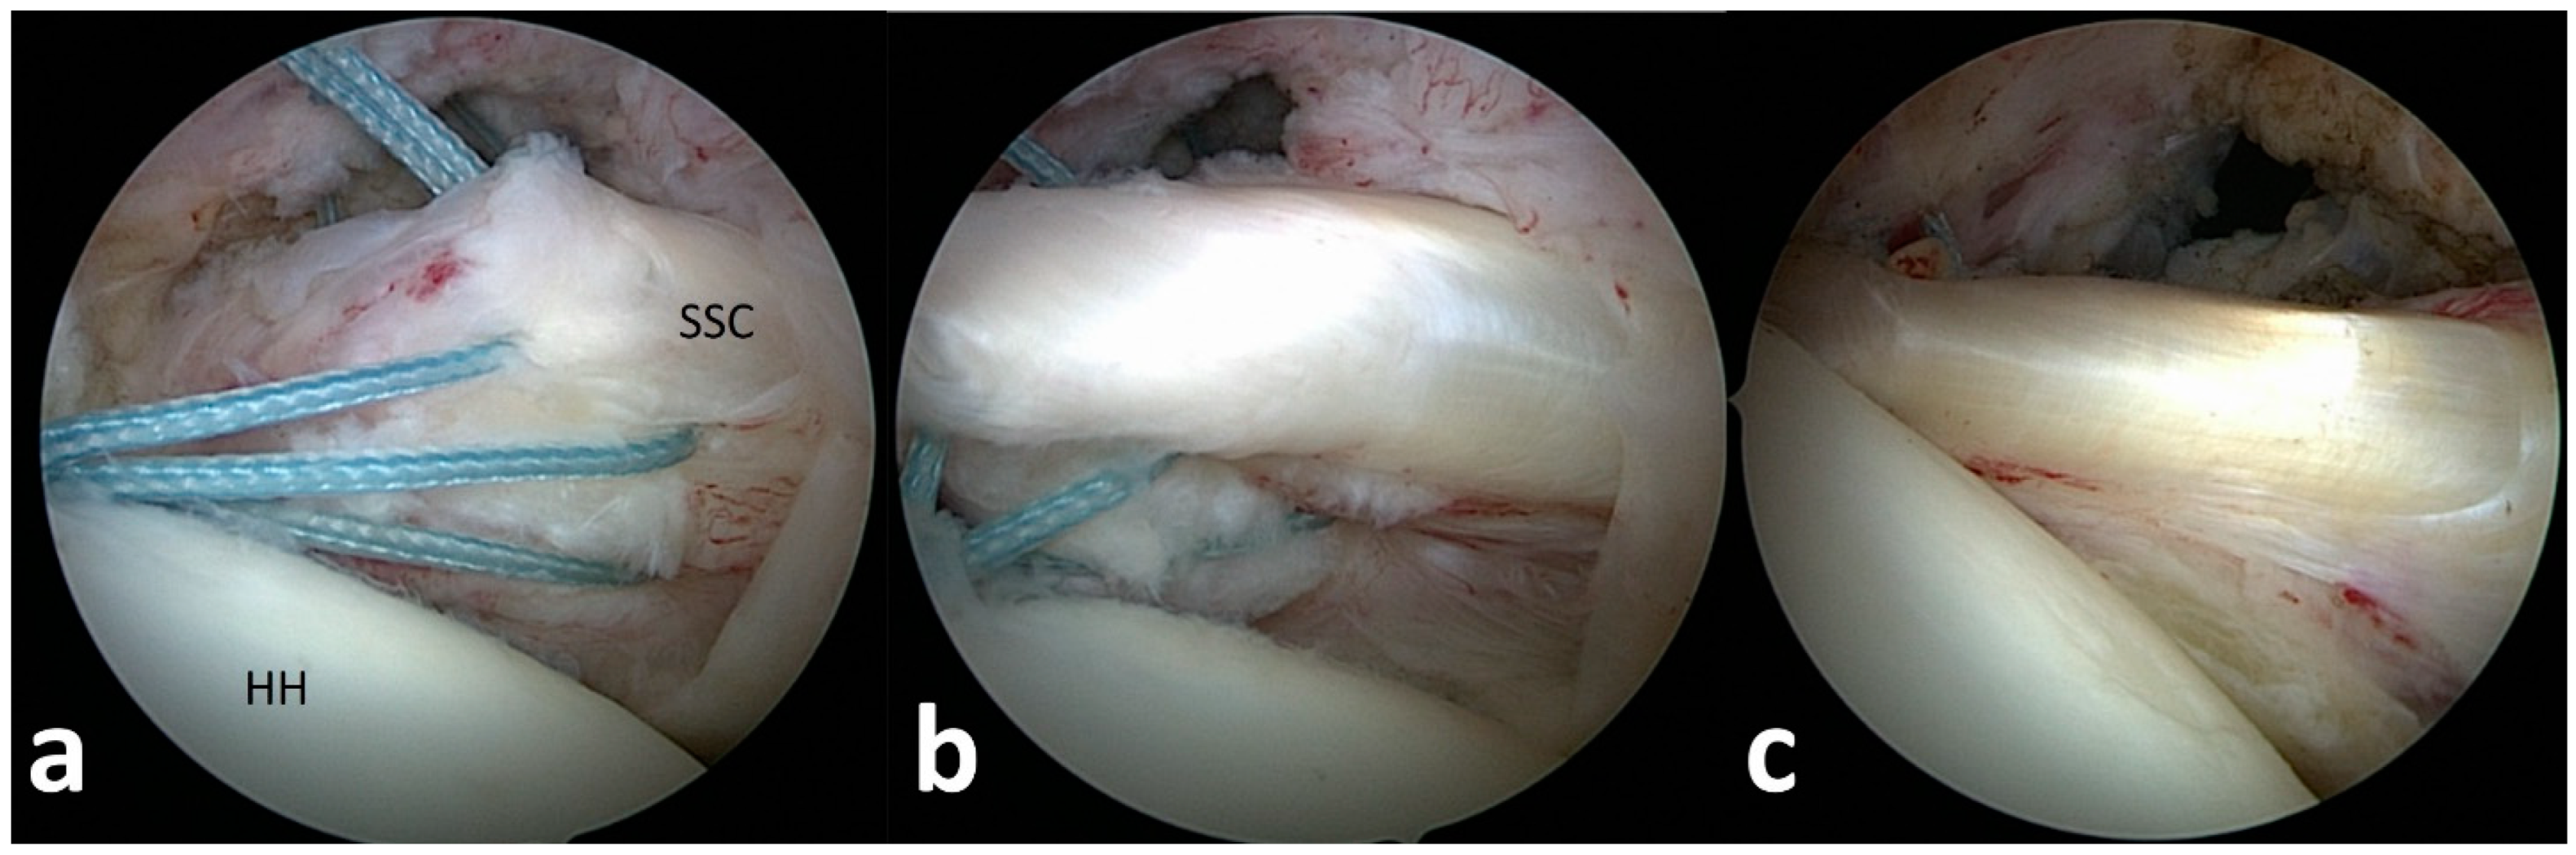

For tendon mobilization, footprint preparation and anchor insertion, additional anterior and anterolateral portals were established, and the subscapularis tendon edge was identified from the lateral portal (Figure 2). In the case of non-retracted tears of the subscapularis tendon, the connection to the transverse ligament was released for tear confirmation. Retracted tendons were released from scar tissue at the scapular neck, the upper tear margin and anterior scarring to the subcoracoid bursa. The mobilized tendon edge was then pulled with traction sutures to the footprint area at the lesser tuberosity.

Following footprint preparation, one to three anchors, depending on the size of the lesion, were placed from inferior to superior at the lesser tuberosity, and the tendons were fixed with knots after perforation with a suture passer (Figure 2, Video S1).

Figure 2. (ac). Arthroscopic subscapularis repair technique. (a) Arthroscopic tendon identification and release of a type 3 subscapularis tear. (b) Arthroscopic tendon mobilization to the lesser tuberosity. (c) View from posterior after tendon refixation at the footprint.